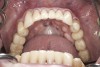

(16.) Preoperative mandibular, occlusal view.

Figure 16